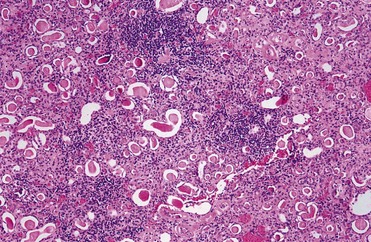

Renal obstruction produces tubular atrophy and cell death. The major mechanism by which tubular cells die is apoptosis, a process that is normally involved in postnatal development and tissue renewal in adults. The process can be triggered by both intrinsic and extrinsic factors and results in degradation and condensation of the nucleus. The cells are further degraded into apoptotic bodies, which are eventually phagocytized by healthy cells, usually without inducing inflammation. When rat kidneys are obstructed, renal tubular cell apoptosis begins in about 4 days and peaks after 15 days, with interstitial cell apoptosis continuing for the duration of obstruction (Choi et al, 2000). Glomerular cells appear to be resistant to obstruction-induced apoptosis. Pathological apoptosis of tubule cells from obstruction may secondarily trigger inflammatory responses from the release of cytokines and recruitment of leukocytes (Canbay et al, 2004).

Urinary tract obstruction leads to progressive and, eventually, permanent changes in the structure of the kidney, including the development of tubulointerstitial fibrosis, tubular atrophy and apoptosis, and interstitial inflammation. A number of cytokines and growth factors have been shown to play roles in these events, among which the most prominent include transforming growth factor beta TGF-β, angiotensin II, NFκB, and TNF-α. Some are produced directly from the renal tubular and interstitial cells; others are generated from infiltrating macrophages.

Tubulointerstitial fibrosis develops as a consequence of extracellular matrix being synthesized and deposited at a greater rate than it is degraded, as well as to a relative increase in matrix due to collapse of parenchymal volume as nephrons are destroyed (Hewitson, 2009). A family of enzymes known as matrix metalloproteinases (MMPs), which includes collagenase, normally cleaves and degrades the collagenous and noncollagenous components of the extracellular matrix. Obstruction increases the synthesis of tissue inhibitors of metalloproteinases (TIMPs) that reduce MMP activity, resulting in the accumulation of extracellular matrix. Infiltrating macrophages stimulate TGF-β synthesis, and this growth factor increases TIMP production, thus reducing collagen turnover. Macrophages also produce other cytokines and growth factors, such as interleukin 2, interleukin 6, fibroblast growth factor, and platelet-derived growth factor (PDGF), that appear to contribute to this inflammatory and fibrotic process. Active TGF-β binds directly to its type 2 receptor, which subsequently activates and phosphorylates the type 1 TGF-β receptor. Both of these receptors have been shown to be upregulated in rats with UUO, in both the obstructed and contralateral renal units. This may be a factor in the hypertrophic response sometimes seen in the nonobstructed kidney (Sutaria et al, 1998). The activated type 1 TGF-β receptor subsequently phosphorylates SMAD (mobile transcription factors with a name derived from related genes in Caenorhabditis elegans [Sma] and Drosophila [Mad]) proteins. A heteromeric complex of SMAD proteins translocates to the nucleus, where it interacts with transcription factors to regulate gene transcription (Wamsley-Davis et al, 2004) and stimulates tubulointerstitial fibrosis (Fukasawa et al, 2004). Stimulation of TGF-β furthermore stimulates the JNK1 (c-JUN N-terminal protein kinase 1) pathway, which targets the activation of c-Jun and activates transcription factor 2, which are critical components in activating fibronectin production. Increased mRNA expression of TGF-β is seen as early as 10 hours after obstruction and increases for 4 days (Walton et al, 1992; Diamond et al, 1994). The increase occurs primarily in medullary tubules and the interstitium and is less prominent in cortical tubules or glomeruli. Furthermore, TGF-β interacts with other profibrotic growth factors such as EGF and angiotensin II (Kaneto et al, 1993; Ishidoya et al, 1995; Chevalier et al, 1998).

In summary, obstruction of normal urine outflow results in biochemical, immunologic, hemodynamic, and functional changes. It stimulates a cascade in which elevated levels of angiotensin II, cytokines, and growth factors lead to tubular cell apoptosis and cellular inflammation, increased net matrix formation, and tubulointerstitial fibrosis. Many of the mediators are intrinsic to the renal tubular cells, whereas others are contributed by fibroblasts and by migrating macrophages (Fig. 40–3).